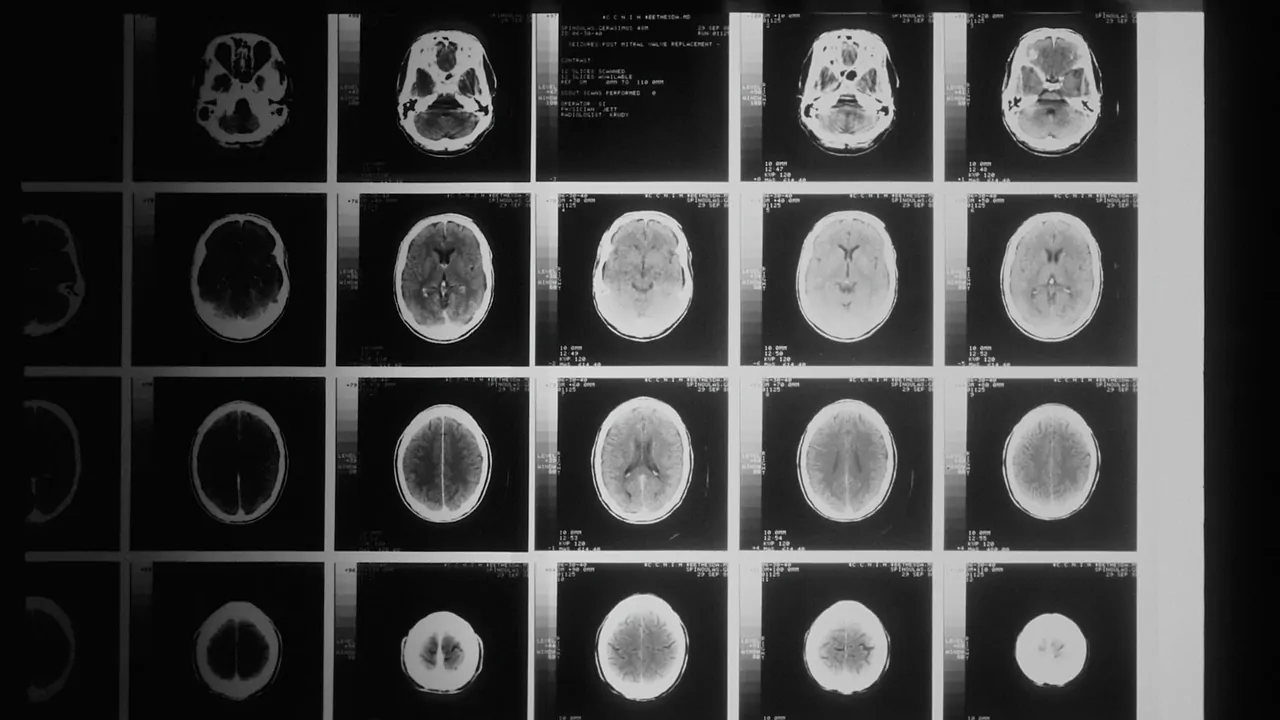

由于大脑富含神经细胞(神经元),因此它是最需要能量的器官,需要持续供应氧气和葡萄糖。 虽然大脑只占身体质量的 2%,但在休息时却消耗了 20% 至 30% 的能量。 这就是为什么创伤和头部受伤病例的一线院前治疗是提供 100% 的氧气。 之前的研究表明,大脑功能会受到供氧水平的影响。